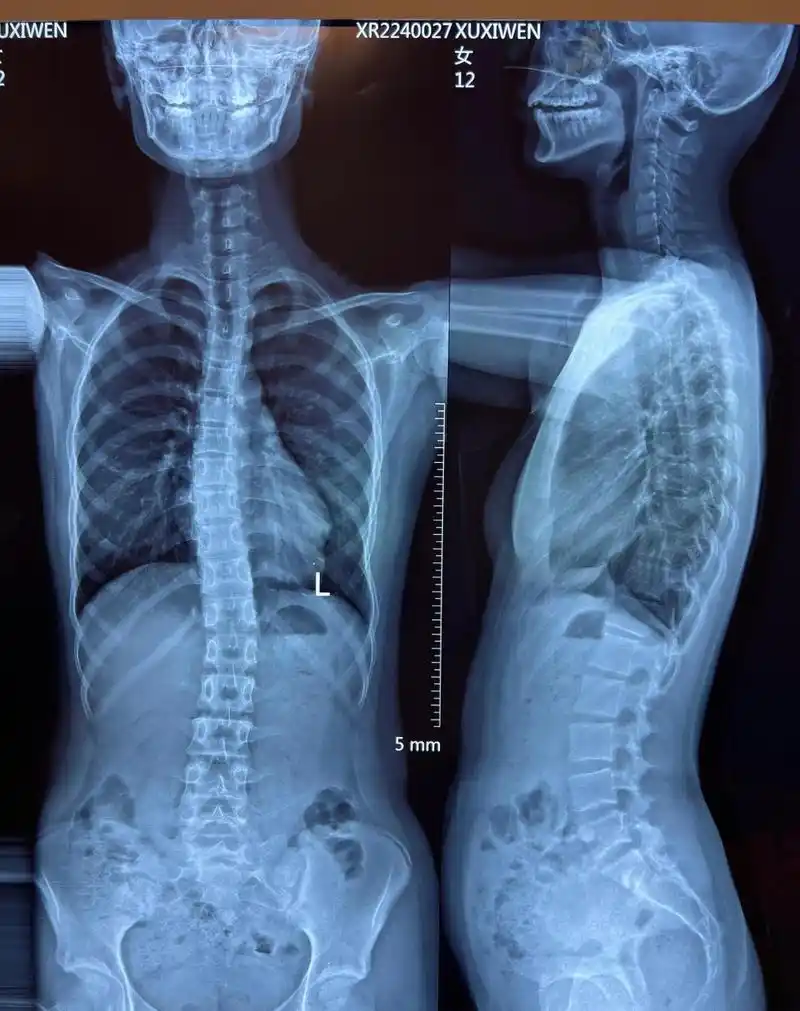

蝴蝶骨是好还是坏,美丽的骨骼曲线并非疾病(可能是驼背导致)